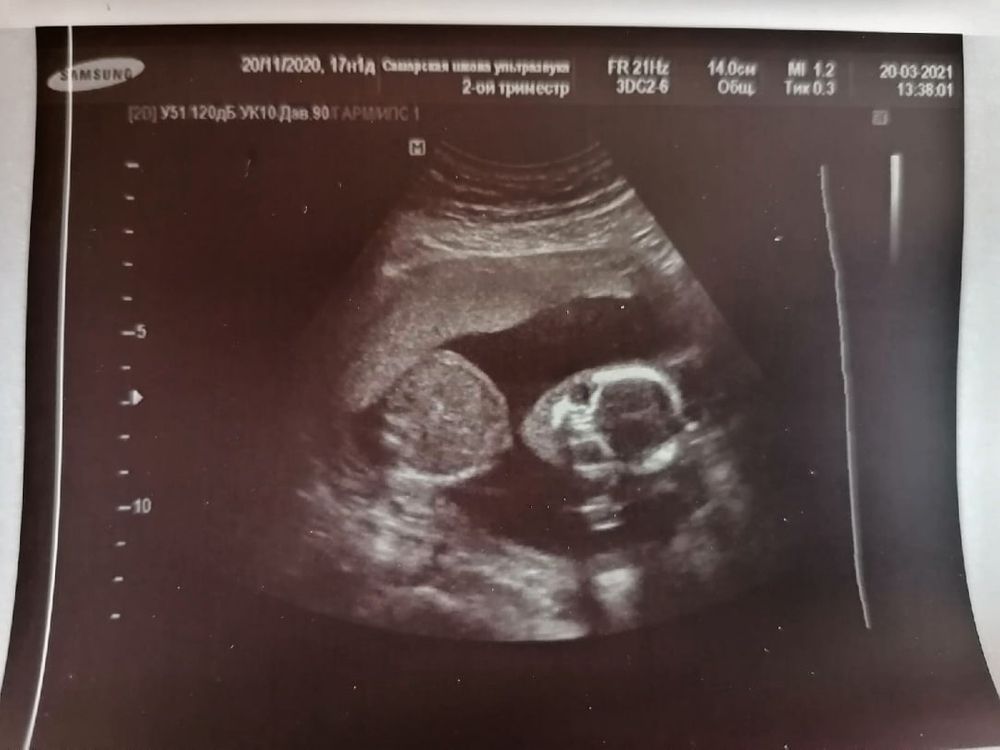

И вот сегодня, в 17+1 с мужем поехали на узи с целью точно узнать, кто же у нас. И сразу же без всяких сомнений узистка сообщила, что это девочка и никакого мальчика она и близко не видит 😄 Малышка позволила рассмотреть себя во всей красе, а потом многозначительно отвернулась мол хватит)))) Моя звезда❤️